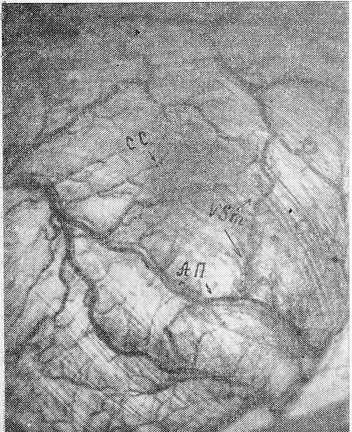

Трансиллюминация обеспечивает выявление интрамуральных сосудов, принадлежащих субсерозному, мышечному, подслизистому слоям и слизистой. Картина внутристеночных сосудистых сетей представлена на рис. 5. Подслизистое сплетение формируется за счет ветвей различного калибра. Видны анастомозы смежных ветвей и производных сосудов, принадлежащих той же ветви. Этот основной коллектор кровотока включает сосуды, расположенные в различных плоскостях. О положении ветвей в толще стенки можно судить по их контрастности. Ветви, лежащие ближе к серозному покрову, имеют более отчетливые контуры.

Рис. 5. Передняя стенка слепой кишки. Подслизистое сосудистое сплетение противобрыжеечного края слепой кишки. Внеполостная трансиллюминация (препарат)

АП — анастомотический пояс, СС — сосуды слизистой, vsm — сосуды подслизистой.